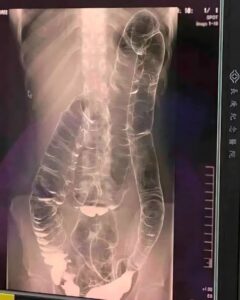

Peste două săptămâni fără scaun au adus o tânără la Urgențe, iar investigațiile au dezvăluit un tablou rar și alarmant: colonul era atât de dilatat încât urca până aproape de inimă, cu pierderea pliurilor caracteristice și aspect neted, semn al unei presiuni interne extreme. Imaginile au devenit motiv de îngrijorare reală pentru medici.

În situații de stagnare prelungită a reziduurilor, colonul este forțat să se lărgească pentru a face loc conținutului reținut. În cazul acestei paciente, întinderea severă a pereților intestinali a transformat un organ flexibil într-unul rigidizat și lipsit de ondulațiile obișnuite. Această transformare reduce capacitatea de contracție și întreține cercul vicios al constipației.

Chiar dacă frecvența tranzitului variază de la o persoană la alta, pauze repetate de peste 3 zile fără scaun reprezintă un motiv de atenție medicală. În contextul prezentat, volumul crescut al colonului și absența pliurilor au fost indicii clare pentru o evaluare imagistică și monitorizare de aproape.